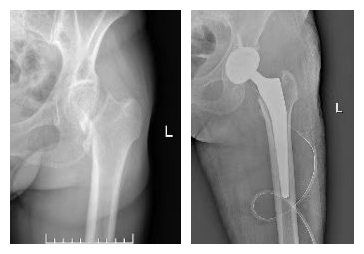

股骨颈骨折全髋关节置换手术